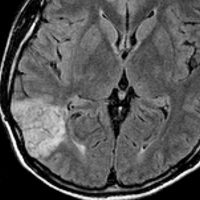

10歳でてんかん発症して難治性になった例